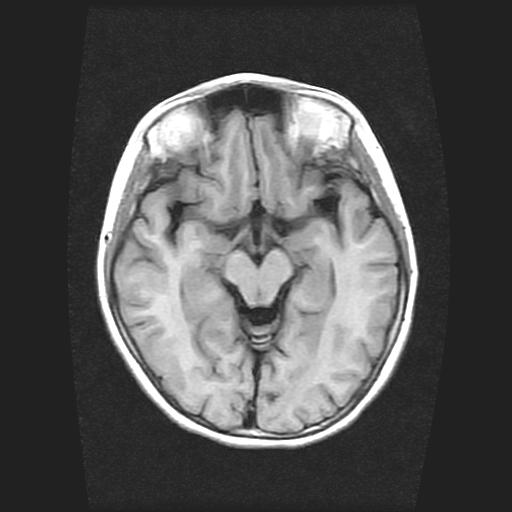

9岁女孩,三岁时诊断为癫痫,一直服丙戊酸钠,现患者一般情况良好,家长复查核磁片,看能否停药..

巨脑回